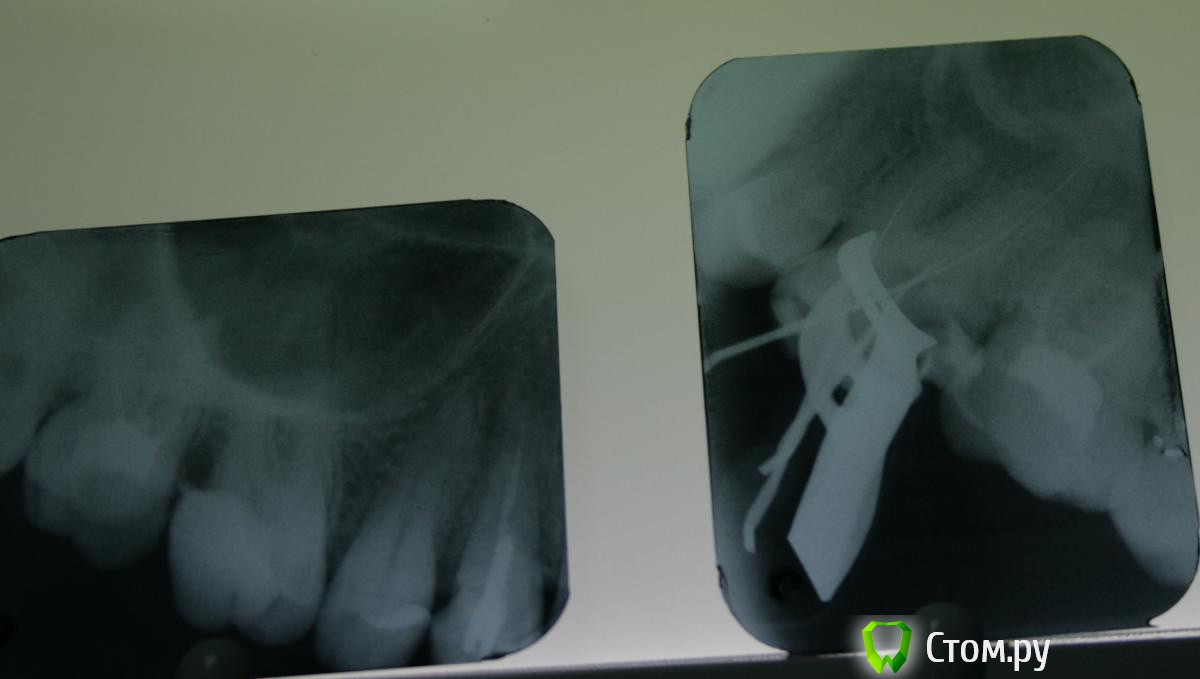

St. Опубликовано 7 ноября, 2014 Автор Поделиться Опубликовано 7 ноября, 2014 Покритикуйте, кому не лень ! Пациентка, в другом учреждении поставили пломбу. Предупредили, что если разболится депульпировать. Разболелся ночью. Попала ко мне по острой боли. Пульпит.Вскрыла - под пломбой чуть мягкого дентина и провалилась в камеру. Ковровая дорожка 10, 15, 20. Мб2 нашла устье, пройти не смогла. Протейперы до Ф1. Хлорка. Кальций. Вр.пломба.Второй визит. Лимонная к-та, гипохлорит. Попыталась ещё пройти мб2 - не смогла. Ещё хлорка, перекись, вода, хлоргексидин. Пломбировка латералкой АН+ и гутта. Апикально мщ -25, дщ - 30.02, небный -35.02.З.ы. смушает средняя треть мщ канала и непройденный мб2.. Ссылка на комментарий

St. Опубликовано 7 ноября, 2014 Автор Поделиться Опубликовано 7 ноября, 2014 Вот ещё. Тут вроде симпатично вышло. Жалобы на боли при накусывании. Перкуссия +++. Термопроба -.Зуб на половину состоит из пломбы. лечен со слов несколько лет назад. Симптоматический апикальный периодонтит 21.Ковровая дорожка. ПроТейпры до ф1. Апикально 50.02. Гипохлорит, перекись, хлоргексидин, эдта. Пломбировка Латералкой. Думала триоксидентом сперва, но получила хороший апмкальный упор и канал высушился без проблем. Поэтому гутта. 6 Ссылка на комментарий